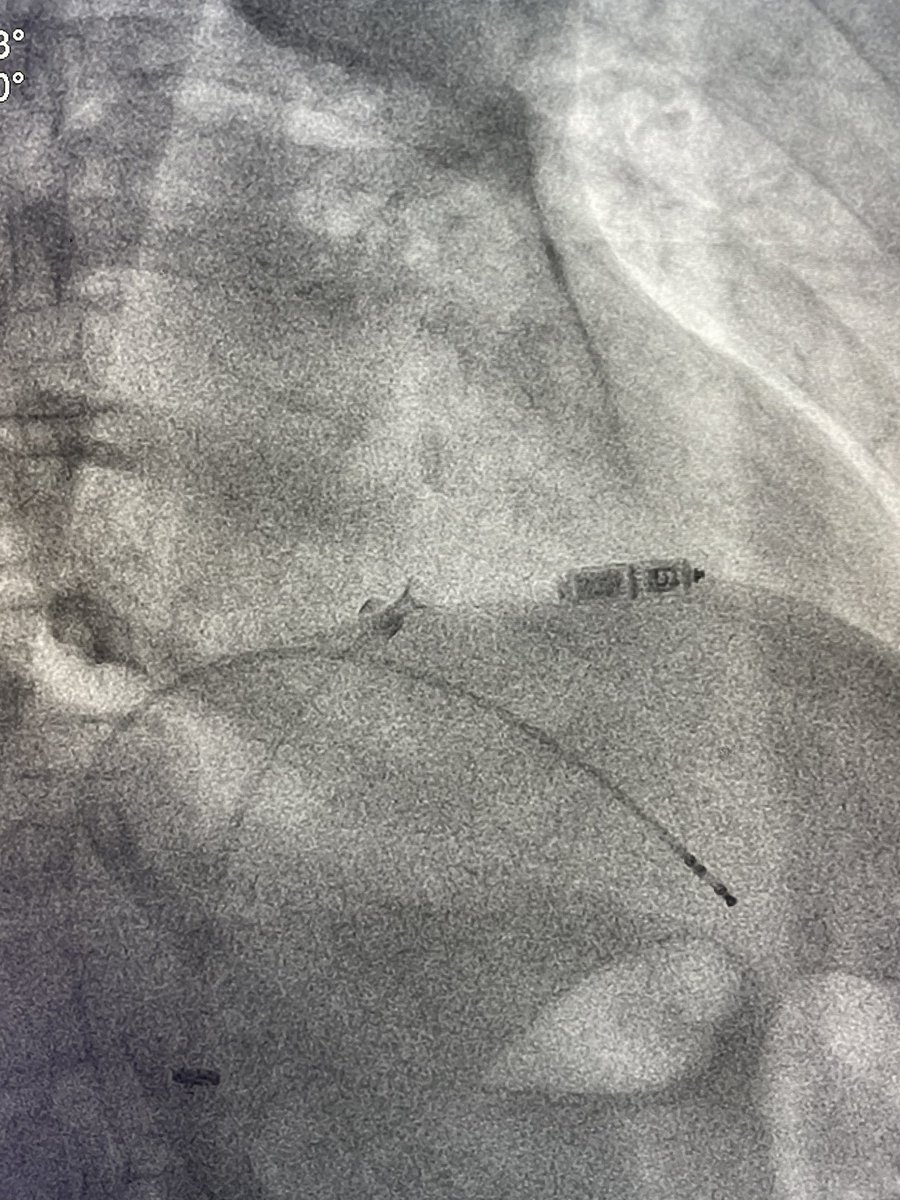

Parahisian PVC, always a challenge to ablate arrhythmias in this region. “We aware of your neighbors @DrFerminGarcia used to say”. Ablated from RCC. @andresenriqueza @FellowEP @DrRoderickTung @hhuang123